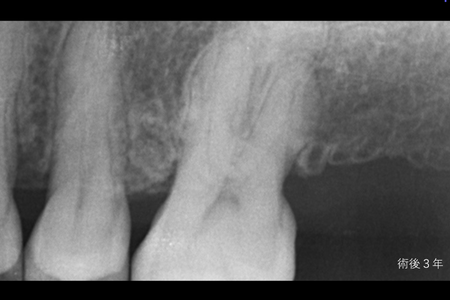

治療名 【重度歯周病】歯周組織再生療法による機能回復 治療期間 約1年(初期治療・経過観察期間含む) 執刀医 Dr. 大杉 治療費 250,000円(税込) 治療解説 一般的に抜歯適応と診断されやすい状態でしたが、歯の保存を優先して歯周組織再生療法を行いました。

事前にプラークコントロールと歯石除去を徹底し、炎症を安定させたうえで外科処置を実施。

結果として抜歯を回避し、長期的な機能維持を目指せる状態へ改善しました。リスク・副作用 術後に一時的な腫れや痛みが生じることがあります(鎮痛剤等の処方で管理を行います)。